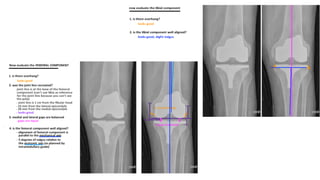

• STANDING XRAY OF KNEE AP AND LATERAL VIEW

APXRAYOFKNEE